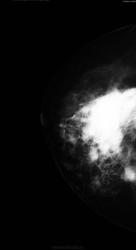

Обратилась дама. Жалоб нет. Чего бы ей написать?

Это коммерсанты в 90-годы парафин ввели или силикон.